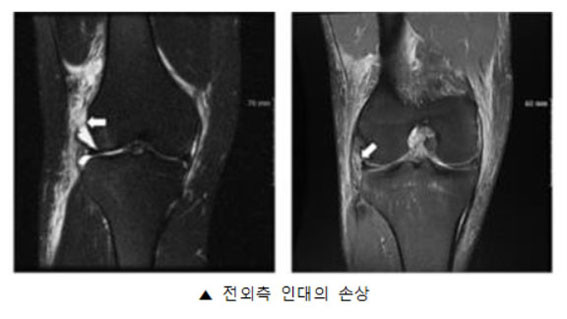

| | ¨Ï ¿Â¾ç½Å¹® | ¾Æ»êÃæ¹«º´¿ø Á¤Çü¿Ü°ú À¯À缺 ±³¼ö°¡ Á¦ 1ÀúÀڷμ Àδë Àç°Ç¼ú¿¡¼ Àü¿ÜÃø Àδ뿡 ´ëÇÑ ¿¬±¸·Î ±¹Á¦ ÇмúÁö¿¡ ³í¹®À» ¹ßÇ¥Çß´Ù.

Á¤Çü¿Ü°ú °ü·Ã SCI(E)±Þ ±¹Á¦ÇмúÁöÀÎ ¡®The Knee¡¯¿¡ °ÔÀçµÈ ¡®Influence of anterolateral ligament injuries on stability and second-look arthroscopic findings¡¯ ³í¹®Àº Àδë Àç°Ç¼ú¿¡¼ Àü¿ÜÃø ÀÎ´ë ¼Õ»óÀÌ Àδë Àç°Ç¼ú¿¡ ¹ÌÄ¡´Â ÀÓ»óÀû ¹æ»ç¼±ÇÐÀû °á°ú¿¡ ´ëÇØ º¸°íÇÑ ³í¹®ÀÌ´Ù.